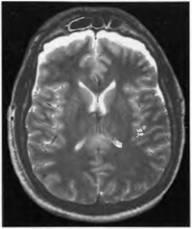

Az Advent MRI lehetővé vált élettartam diagnózisa diffúz axon degenerációt, amely meghatározza azt a pontot vérzéses gócok, illetve zsebeket, a helyi károsodások a fehérállomány az agy, a corpus callosum, a bazális ganglionok és a törzs (ábra. 23, 24). Egy vizsgálatban ezen betegek, MRI kimutatta, nagyobb számú központi változások, mint a CT, de bizonyos esetekben, gócos változások nem észlelhetők CT vagy MRI. MRI szakaszok vérzéses komponenst és ezek nélkül a leggyakrabban észlelt periventrikuláris területén az első és a hátsó szarv az oldalsó agykamrák, a corpus callosum, valamint a terület a középagy. Ezt követően vannak jelei a atrophiás folyamat kiterjesztéseként convexital szubarachnoidális rések, előnyösen a fronto-temporális területek és ventrikuláris rendszerébe. Focal parenchymás változások láthatóvá válnak a kis ciszták CT és MR hasonló tulajdonságokkal agy-gerincvelői folyadék. Axon sérülés, amelyet nem kísér vérzés tomogramokat T2 néz ki, mint egy nagy MR jel sávban.